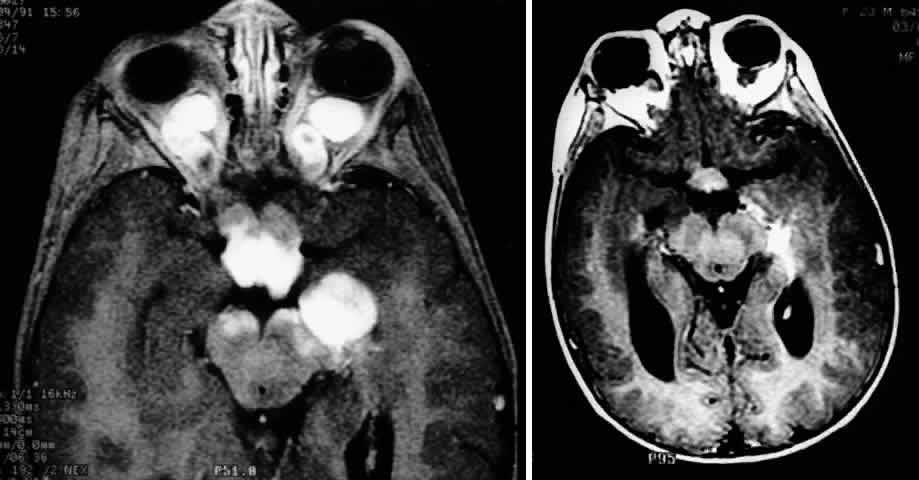

MRI has replaced CT scanning as the optimum test for imaging optic gliomas (Fig. 4 A and B). Optic gliomas have normal to slightly prolonged T1 relaxation times and appear isointense to slightly hypointense to normal brain on T1. Because many of these tumors have prolonged T2 relaxation times, images that are T2 weighted may be used to assess gross tumor margins and posterior extension.72 Optic nerve gliomas often demonstrate minimal enhancement after administration of contrast. To improve MR imaging of optic nerve lesions, a gadopentetate dimeglumine enhancement technique combined with fat suppression can be utilized. Unlike meningiomas, the thickened sheath from arachnoid hyperplasia associated with gliomas will not enhance.77 Although imaging should initially be performed in the axial plane to allow visualization of both the optic nerve and the posterior optic pathways, sagittal views are helpful in demonstrating chiasmal involvement; coronal views can be utilized to delineate intracanalicular tumor.78

Fig. 4. A. T1-weighted sagittal MRI of a patient with neurofibromatosis type 1, demonstrating enlarged optic chiasm consistent with optic glioma. B. T1-weighted coronal image with gadolinium and fat suppression in the same patient, demonstrating the chiasmal glioma.

MRI has several advantages over CT scanning. In addition to sparing children from exposure to ionizing radiation when multiple scans are required, MRI eliminates bony artifact and is superior in evaluating the intracanalicular, chiasmal, and postchiasmal extension of the tumor.78 Brown and associates79 reported 10 posteriorly located lesions by MRI, none of which were visualized by CT. Anterior pathway lesions were detected with equal sensitivity by both modalities. Unfortunately, microscopic spread of gliomas can go undetected by both CT and MRI.

In addition to detecting bilateral optic nerve glioma, other MRI findings can suggest an association between an optic nerve glioma and NF-1. One imaging characteristic to watch for is double-intensity tubular thickening, which is seen as a high T2 signal surrounding the optic nerve. This radiologic finding has been termed a “pseudo-CSF” signal and can be misinterpreted as cerebrospinal fluid in a dilated subarachnoid space.80 The high T2 signal arises from perineural arachnoidal gliomatosis, a histopathologic pattern most commonly seen in NF-1-associated gliomas.60 Elongation of the nerve secondary to axial growth of the perineural tumor as well as downward kinking of the nerve in the midorbit are other features suggestive of NF-1-related gliomas.80 Neuroimaging studies have demonstrated that NF-1 patients may have more extensive glioma involvement of the visual pathway than patients who do not have NF-1.79,81 Despite this difference in visual pathway involvement, the same investigators81 noted a lower incidence of progressive neurologic deficits and visual symptoms in NF-1-related glioma patients compared with patients whose gliomas were unrelated to NF-1. MRI scanning of NF-1 patients may also demonstrate aqueductal stenosis, idiopathic macrocephaly, and unidentified T2-weighted signals in the basal ganglia, internal capsule, midbrain, cerebellum, and subcortical white matter.51,64,82